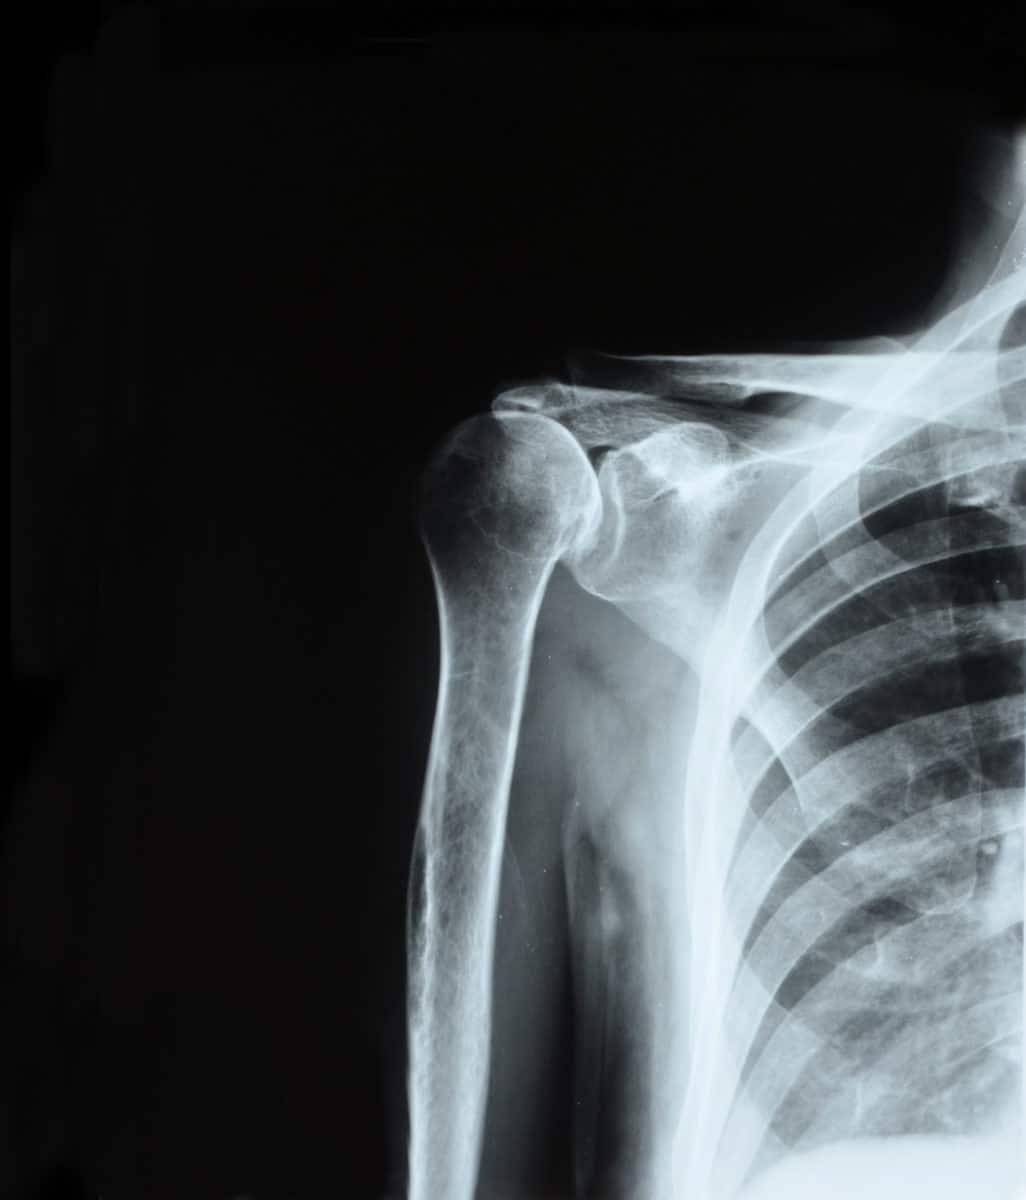

When you book your initial appointment with our team, we will begin by evaluating the state of your shoulder. This will include taking your medical history, performing a physical examination, and possibly taking X-rays. Physical exams help us to do two things: pinpoint the source of your pain and evaluate your range of motion.

We will also ask about your past shoulder problems, if you have had any. Specifically, we will ask about your pain level, range of motion, and any prior treatments you have had. Then, we may take X-rays to reveal damage or trauma to your shoulder joint. Imaging tests help us to determine which treatment is best for your situation.

The shoulder joint is a ball and socket joint made up of three main bones: the upper arm bone (humerus), collarbone (clavicle), and shoulder blade (scapula). Within the joint as a whole, there are actually two joints. These are the acromioclavicular and glenohumeral joints. The acromioclavicular joint is where the highest part of the scapula meets the clavicle.

The glenohumeral joint is where the top of the humerus (humeral head) fits into the glenoid, which is a socket in the scapula. This is what allows such a wide shoulder motion range. Both the ball and socket must be healthy and stable for the shoulder to function properly.